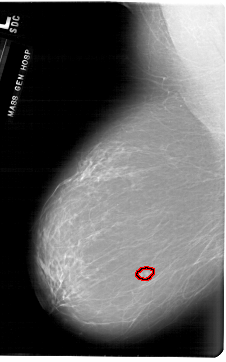

A_1876_1.LEFT_MLO

LEFT_MLO LINES 6871 PIXELS_PER_LINE 4291 BITS_PER_PIXEL 12 RESOLUTION 43.5 OVERLAY

FILE: A_1876_1.LEFT_MLO.OVERLAY

TOTAL_ABNORMALITIES 1

ABNORMALITY 1

LESION_TYPE MASS SHAPE LOBULATED MARGINS MICROLOBULATED

ASSESSMENT 4

SUBTLETY 3

PATHOLOGY BENIGN

TOTAL_OUTLINES 1

BOUNDARY